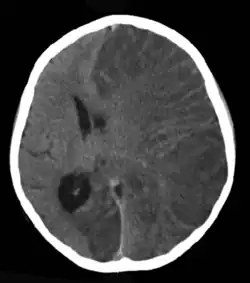

| Brain CT scan without contrast enhancement of a patient, female, 8 years old, with Rasmussen's encephalitis. |